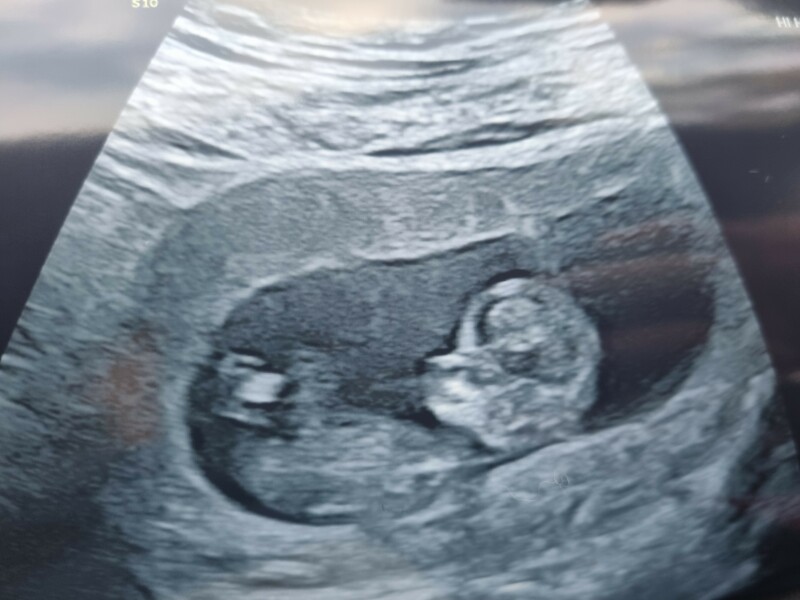

Zaalfruit · 04/11/2022 21:06

@LemonDrizz lovely pic !!

Firefly89 · 05/11/2022 08:11

@LemonDrizz lovely pic I’m also waiting for NIPT test but they said they phone quickly I think in a few days if you at risk so hoping as I haven’t heard anything all is good!